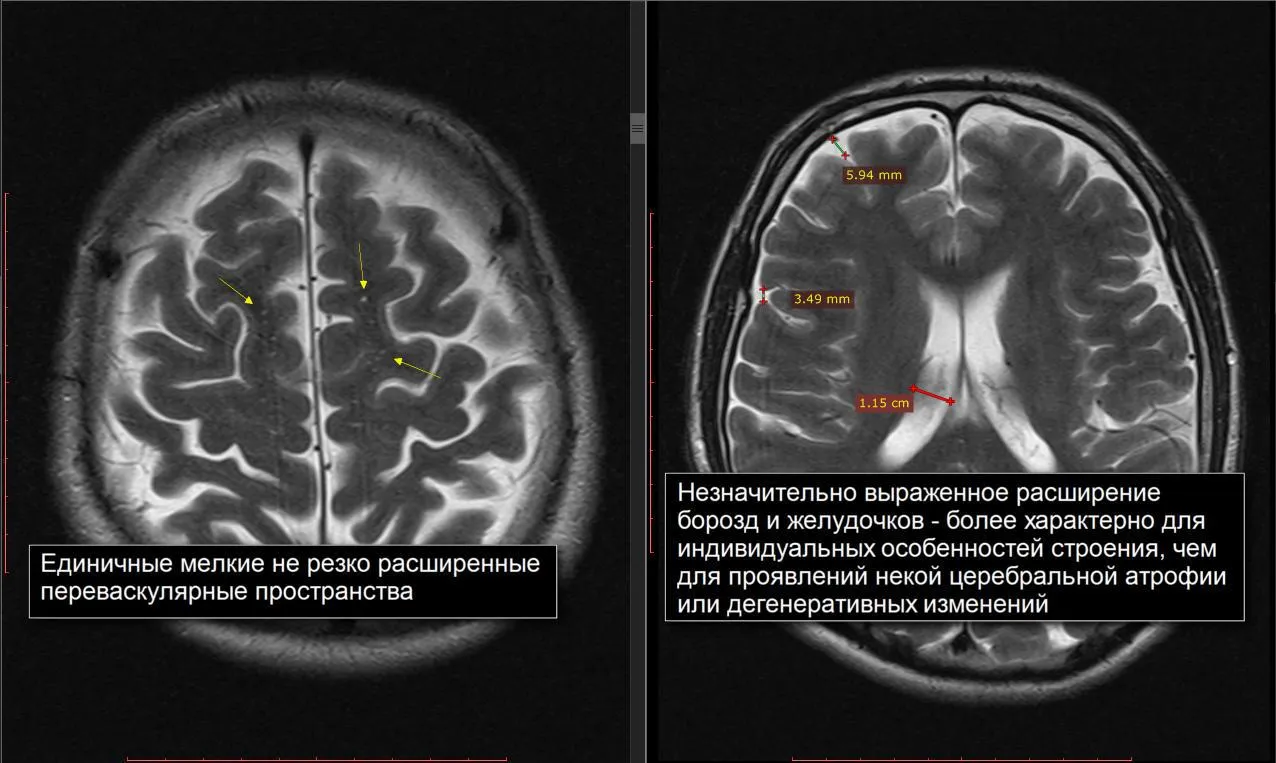

Признаки умеренно выраженной наружная

Признаки умеренно выраженной наружная 113 фото